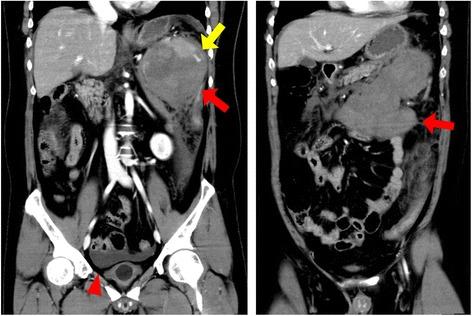

A 33-year-old man suffered sudden abdominal distension without traumatic episodes. He had undergone total splenectomy for hereditary spherocytosis 13 years ago. He was in shock, and his hemoglobin level was 10.5 g/dl. Contrast enhanced computed tomography revealed a giant mass in the left upper abdomen and extravasation of the contrast material into the mass. Excision of the mass was performed, and microscopic examination showed a giant hematoma surrounded by normal splenic tissue. We speculated that an accessory spleen or splenosis had enlarged for the 13 years and ruptured. The patient remained asymptomatic 4 months after the surgery. Spontaneous hemorrhage from accessory spleens or splenosis is extremely rare, and relevant case reports suggest that surgical resection of bleeding sites yields favorable prognosis although preoperative qualitative diagnosis seems to be difficult.

一名33岁男性在无外伤情况下突然出现腹胀。13年前他因遗传性球形红细胞增多症接受了全脾切除术。他处于休克状态,血红蛋白水平为10.5 g/dl。增强计算机断层扫描显示左上腹有一个巨大肿块,造影剂外渗至肿块内。对肿块进行了切除,显微镜检查显示为一个巨大血肿,周围是正常脾组织。我们推测一个副脾或脾组织植入物在13年里逐渐增大并破裂。患者术后4个月仍无症状。副脾或脾组织植入物自发出血极为罕见,相关病例报告表明,尽管术前定性诊断似乎困难,但对出血部位进行手术切除可获得良好预后。